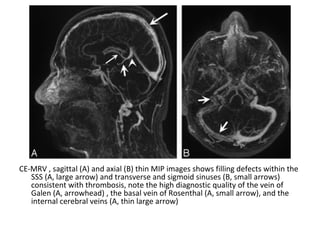

Axial FLAIR (A and B) and DWI (C and D) images at the level of the thalamus

(A & C) and midbrain (B & D) demonstrate infarction of the bilateral

paramedian thalami without midbrain involvement (pattern 2)